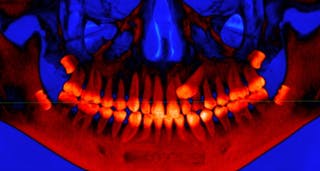

Wie die übrigen Zähne bilden sich auch die Weisheitszähne im Kieferknochen. Aber sie bilden sich erst sehr spät im Vergleich zu unseren anderen Zähnen.

Die Entwicklung der zweiten Backenzähne beginnt etwa im dritten Lebensjahr. Die Weisheitszähne beginnen oft erst im Alter von neun Jahren zu wachsen, aber es gibt große Unterschiede: Sie können schon im Alter von fünf Jahren ausbrechen und bis zu 15 Jahre alt sein. Sie brechen zwischen 17 und 24 Jahren aus dem Zahnfleisch aus, wenn nicht sogar noch früher.

Ein Zahn, der nicht richtig durch das Zahnfleisch und in den Mund durchbricht, ist „impaktiert“. Impaktierte Zähne können mit Problemen wie Zahnfleischerkrankungen, Zysten oder Schäden am zweiten Backenzahn in Verbindung gebracht werden.

Weisheitszähne sind nicht nur die Zähne, die am häufigsten impaktiert werden, sondern auch die Zähne, die sich oft überhaupt nicht bilden.

Der Hauptgrund für eine Impaktion der Weisheitszähne ist Platzmangel im hinteren Teil des Kiefers. Unser Team fand heraus, dass, wenn sich die Weisheitszähne sehr spät entwickeln und durchbrechen, der meiste Platz bereits von den ersten und zweiten Backenzähnen beansprucht wird, so dass sich der Weisheitszahn nicht nach oben und durch das Zahnfleisch bewegen kann.

Ein verwandtes Problem ist das Kieferwachstum und die Gesamtlänge. Wenn der Kiefer nicht lang genug und schnell genug wächst, haben auch die sich später bildenden Weisheitszähne keinen Platz mehr und können nicht richtig oder gar nicht ausbrechen.